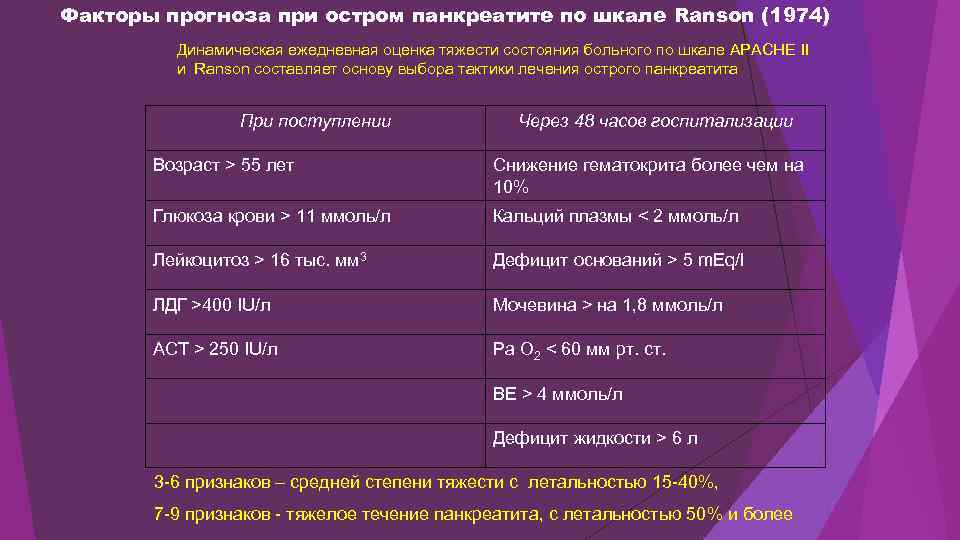

Факторы прогноза при остром панкреатите по шкале Ranson (1974) Динамическая ежедневная оценка тяжести состояния больного по шкале APACHE II и Ranson составляет основу выбора тактики лечения острого панкреатита При поступлении Через 48 часов госпитализации Возраст > 55 лет Снижение гематокрита более чем на 10% Глюкоза крови > 11 ммоль/л Кальций плазмы < 2 ммоль/л Лейкоцитоз > 16 тыс. мм 3 Дефицит оснований > 5 m. Eq/l ЛДГ >400 IU/л Мочевина > на 1, 8 ммоль/л АСТ > 250 IU/л Ра О 2 < 60 мм рт. ст. ВЕ > 4 ммоль/л Дефицит жидкости > 6 л 3 -6 признаков – средней степени тяжести с летальностью 15 -40%, 7 -9 признаков - тяжелое течение панкреатита, с летальностью 50% и более

Факторы прогноза при остром панкреатите по шкале Ranson (1974) Динамическая ежедневная оценка тяжести состояния больного по шкале APACHE II и Ranson составляет основу выбора тактики лечения острого панкреатита При поступлении Через 48 часов госпитализации Возраст > 55 лет Снижение гематокрита более чем на 10% Глюкоза крови > 11 ммоль/л Кальций плазмы < 2 ммоль/л Лейкоцитоз > 16 тыс. мм 3 Дефицит оснований > 5 m. Eq/l ЛДГ >400 IU/л Мочевина > на 1, 8 ммоль/л АСТ > 250 IU/л Ра О 2 < 60 мм рт. ст. ВЕ > 4 ммоль/л Дефицит жидкости > 6 л 3 -6 признаков – средней степени тяжести с летальностью 15 -40%, 7 -9 признаков - тяжелое течение панкреатита, с летальностью 50% и более